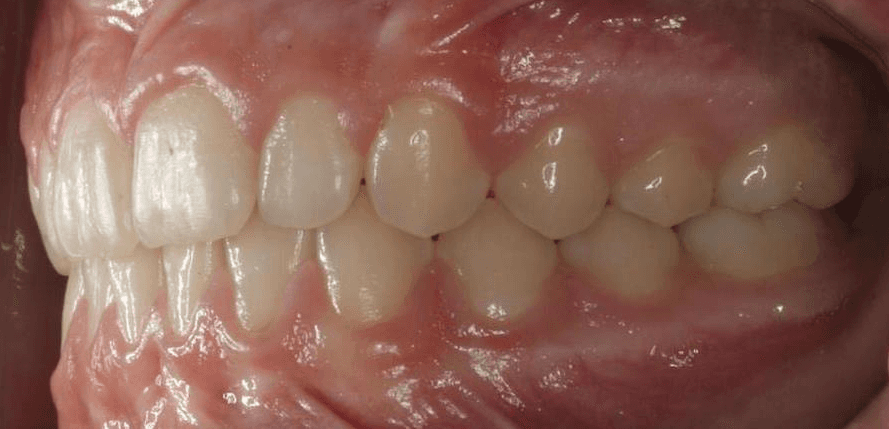

Final results

INTRAORAL